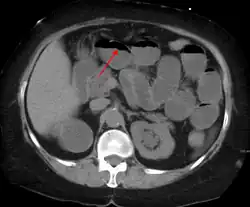

Radiological signs of bowel obstruction include bowel distension (small bowel loops dilated >3 cm) and the presence of multiple (more than 2) air-fluid levels on supine and erect abdominal radiographs.[16] Ultrasounds may be as useful as CT scanning to make the diagnosis.[17]